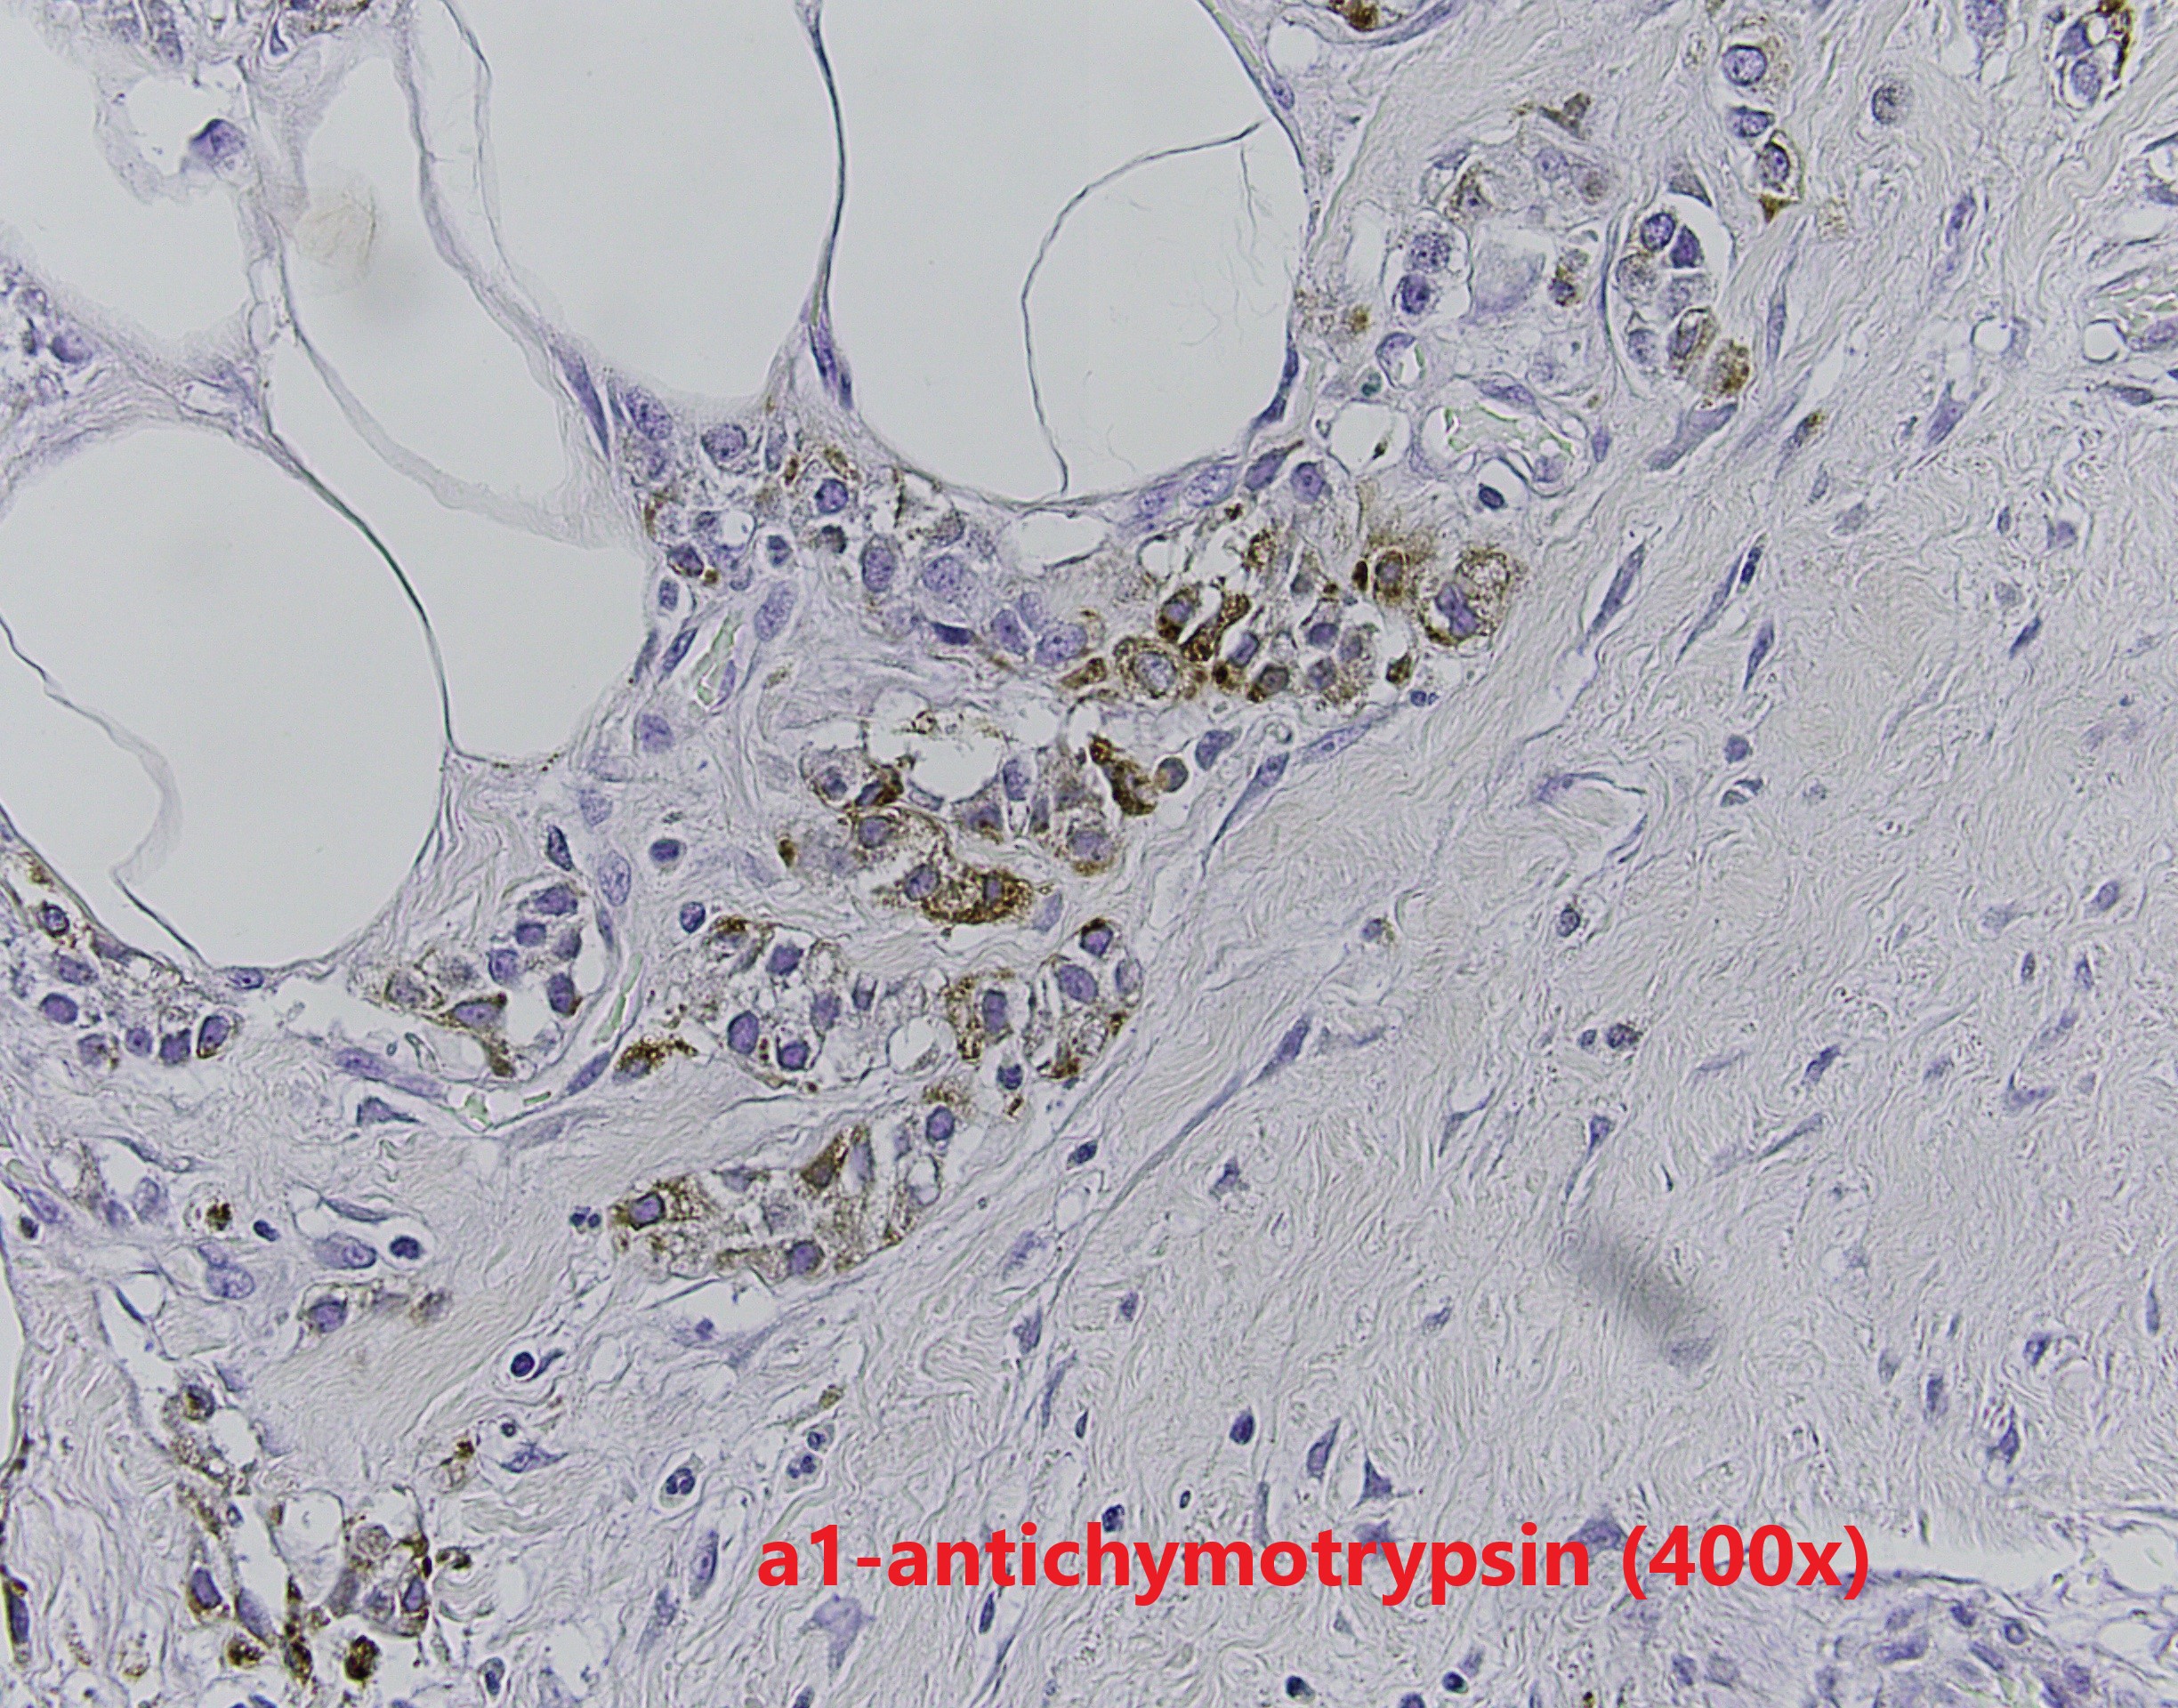

The patient is a middle-aged female with an irregular enhancing mass in the right breast. After resection, IHC revealed GATA3 and CK7 positivity and p63 negativity. Further studies of lysozyme and a1-antichymotrypsin are shown.

Breast acinic cell carcinoma (ACC) is a rare entity and usually affects women aged 20-80 years. Architectural patterns of ACC are variable, ranging from microglandular proliferation to solid. Diagnosis of ACC is mainly based on cytological features. The tumor cells show abundant eosinophilic to clear cytoplasm with coarse granules. The nuclei are usually centrally located with prominent nucleoli. Cytological atypia and mitosis can be seen. The tumor cells are usually triple negative, and positive for S100, EMA, lysozyme and α1-antichymotrypsin. The differential diagnosis is broad depends on cytomorphology. The prognosis of ACC is still unclear because the limited number of cases reported. Most of the reported patient had chemoradiation and surgery.